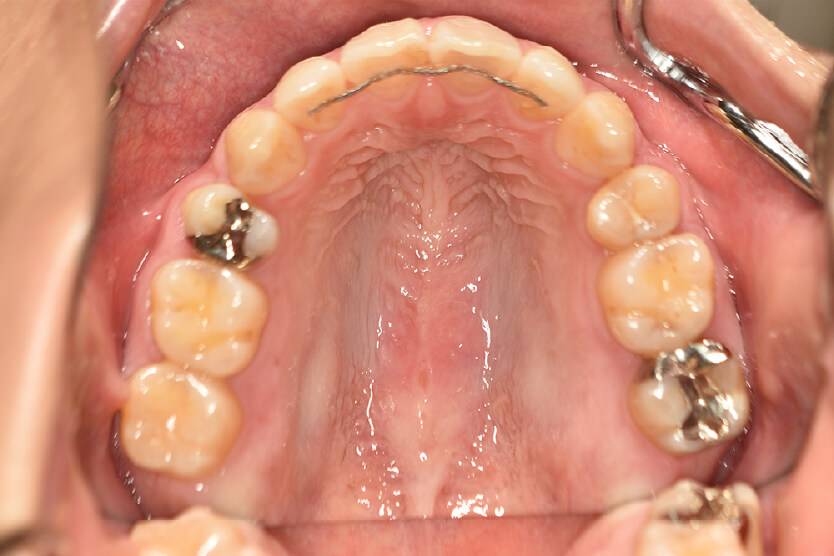

初診時

症例 症例 症例 症例

年齢

21歳 性 別 女性

治療内容の詳細 初診時21歳の女性で、出っ歯、下顎前歯部のがたつきを気にされ来院されました。

検査の結果、上顎前突、上下顎前歯部叢生および開咬を伴うアングルⅡ級1類不正咬合と診断しました。

治療としては、上下左右第一小臼歯を抜歯して、セルフライゲーションブラケット装置(デーモンシステム)とマウスピース型矯正装置(インビザライン)で配列を行いました。

この際、上顎に歯科矯正用アンカースクリューを設置し上顎前歯部後退時の土台としました。

開咬については、顎間ゴムの協力もあり改善されました。